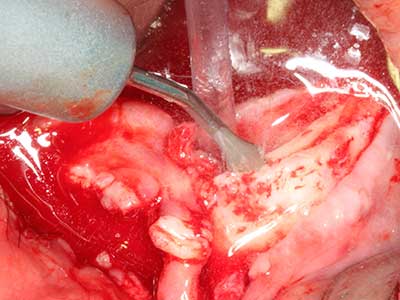

Sollen chirurgische Eingriffe mit unmittelbarer Knochenbeziehung an empfindlichen Strukturen wie Blutgefäßen oder Nerven erfolgen, so bergen rotierende Instrumente ein erhebliches Potential an iatrogener Schädigung. Gerade bei Nervdarstellungen nach iatrogener Schädigung, oder aber im Zuge einer Nervlateralisation für resektive und rekonstruktive Eingriffe oder Implantatinsertionen können piezoelektronische Geräte hilfreich sein Knochendeckel zu präparieren und nervnahe Hartgewebsanteile zu entfernen (Abb. 17-20). Ein leichter Kontakt des Nervstrangs zur Piezospitze bleibt dabei in der Regel folgenlos – allerdings kann eine unvorsichtige Vorgehensweise mit sägeartigen Bewegungen bzw. Ansätzen bei noch vorhandener knöcherner Unterlage durchaus temporäre oder aber auch permanente Nervschädigungen verursachen. Das Risiko einer solchen Schädigung wird jedoch als wesentliche geringer eingeschätzt als unter Anwendung von Säge- oder Fräsinstrumenten (Pereira, Gealh et al. 2014).